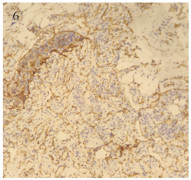

Competing interests: The authors declare that they have no competing interests.作者贡献:王立娟: 论文撰写邹凌凤: 提供病例郭小红: 论文指导曹晓静: 图片制作王军大: 提供影像学图片曾敏: 文章审校 -